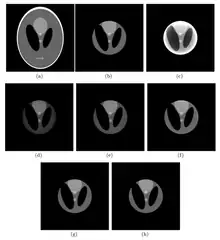

The first interior-reconstruction method listed below is extrapolation. It is a local tomography method which eliminates truncation artifacts but introduces another type of artifact: a bowl effect. An improvement is known as the adaptive extrapolation method, although the iterative extrapolation method below also improves reconstruction results. In some cases, the exact reconstruction can be found for the interior reconstruction. The local inverse method below modifies the local tomography method, and may improve the reconstruction result of the local tomography; the iterative reconstruction method can be applied to interior reconstruction. Among the above methods, extrapolation is often applied.

Extrapolation method

Adaptive extrapolation method

Iterative extrapolation method

Local tomography

Local inverse method

Iterative reconstruction method

Comparison of methods

The extrapolation method is suitable in a situation where

The adaptive extrapolation method is suitable for a situation where

The iterative extrapolation method is suitable for a situation in which

Local tomography is suitable for a situation in which

The local inverse method, identical to local tomography, suitable in a situation in which

The iterative reconstruction method obtains a good result with large calculations. Although the analytic method achieves an exact result, it is only functional in some situations. The fast extrapolation method can get the same results as the other extrapolation methods, and can be applied to the above interior reconstruction methods to reduce the calculation.